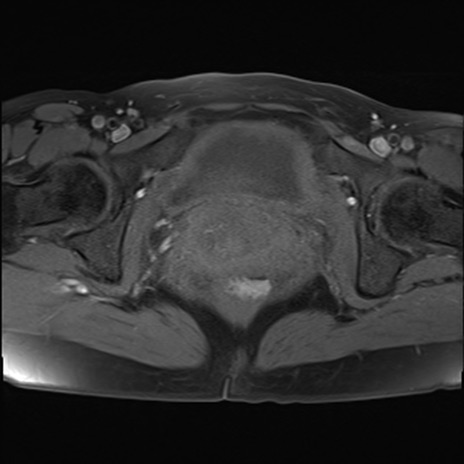

MRI(4日後)

T2WI(横断像)